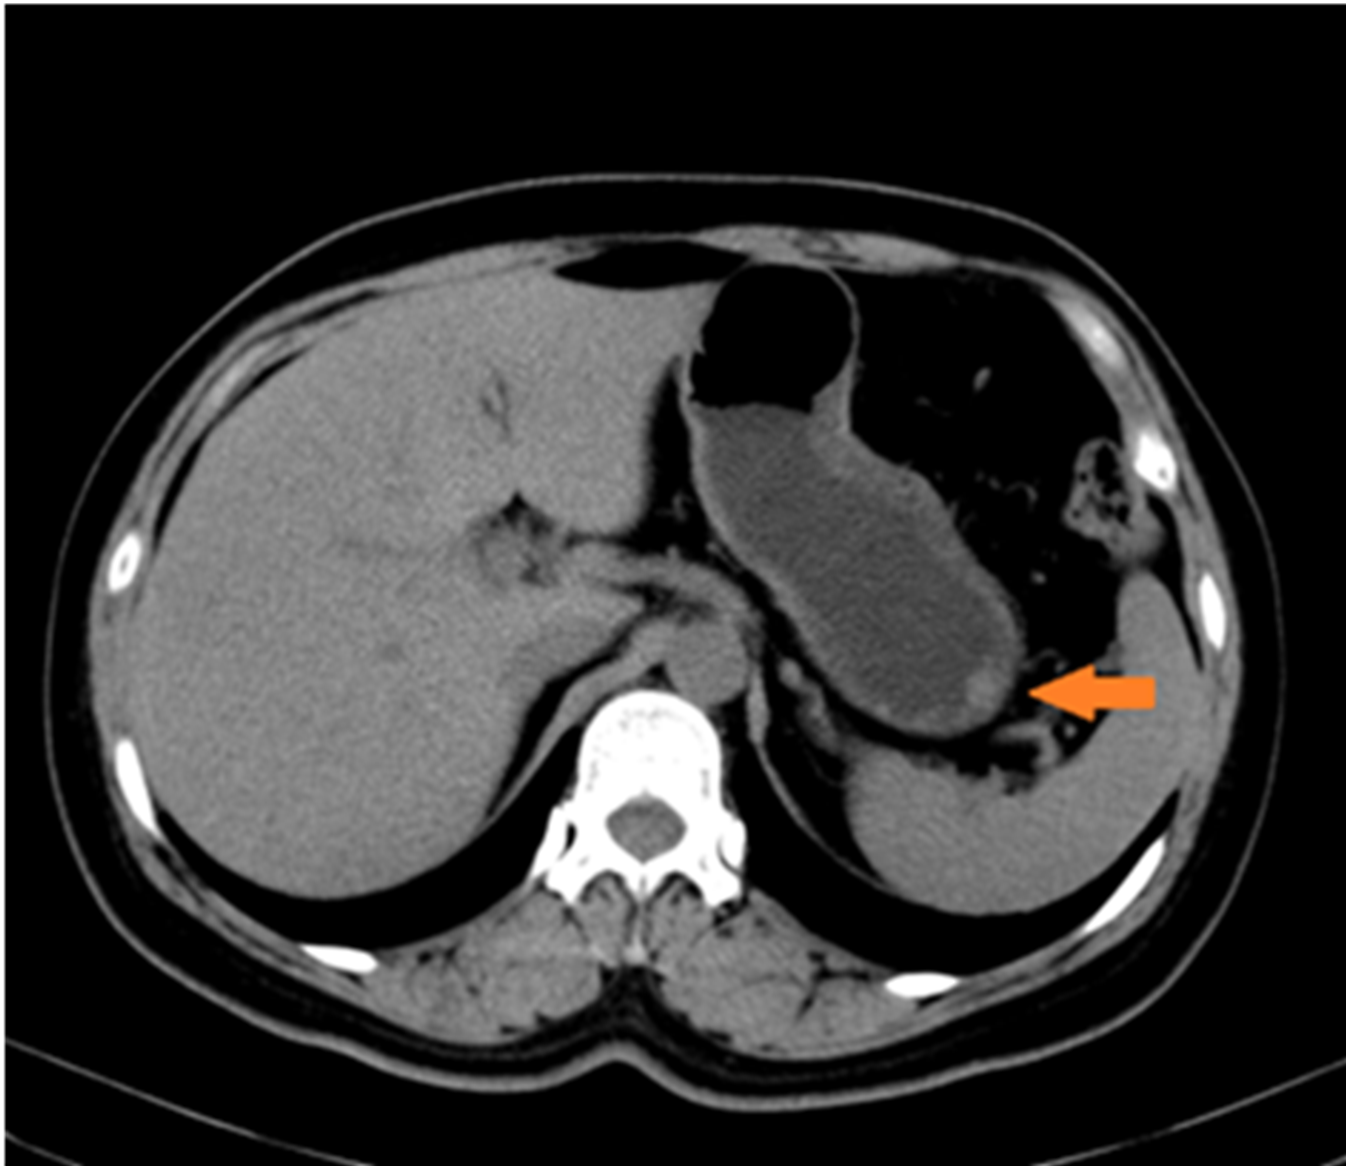

Upon admission, no superficial lymph node enlargement was noted throughout the body, and cardiac, pulmonary, or abdominal examinations showed no abnormal signs. The patient’s past medical, personal, and family histories were unremarkable. Laboratory tests were performed, including blood count, liver and kidney function, electrolytes, carcinoembryonic antigen, cancer antigen 19-9, or alpha fetoprotein. Due to technical limitations, HHV-8 testing cannot be performed. Epigastric CT revealed slight thickening of the lateral wall of the greater curvature and a poorly defined, rounded soft tissue density shadow projecting into the gastric cavity. (Figure 2). Chest CT revealed no evidence of enlarged lymph nodes or pulmonary lesions. Based on the combined findings from the physical examination and chest and abdominal CT imaging, other sites of involvement were preliminarily excluded.

Figure 2

www.frontiersin.org

Figure 2. Radiological findings on the greater curvature of the stomach. Slight thickening of the lateral wall of the greater curvature of the gastric body is observed, presenting as a rounded soft-tissue density shadow.